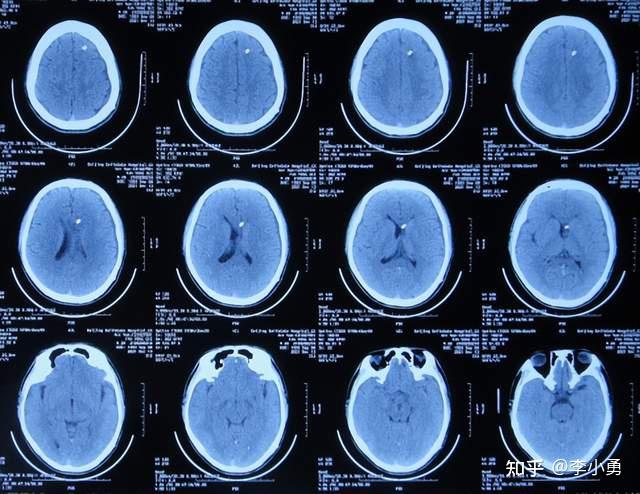

结核脑膜炎性脑积水外院治11天无效后,及早直接转来李小勇脑脊液科治